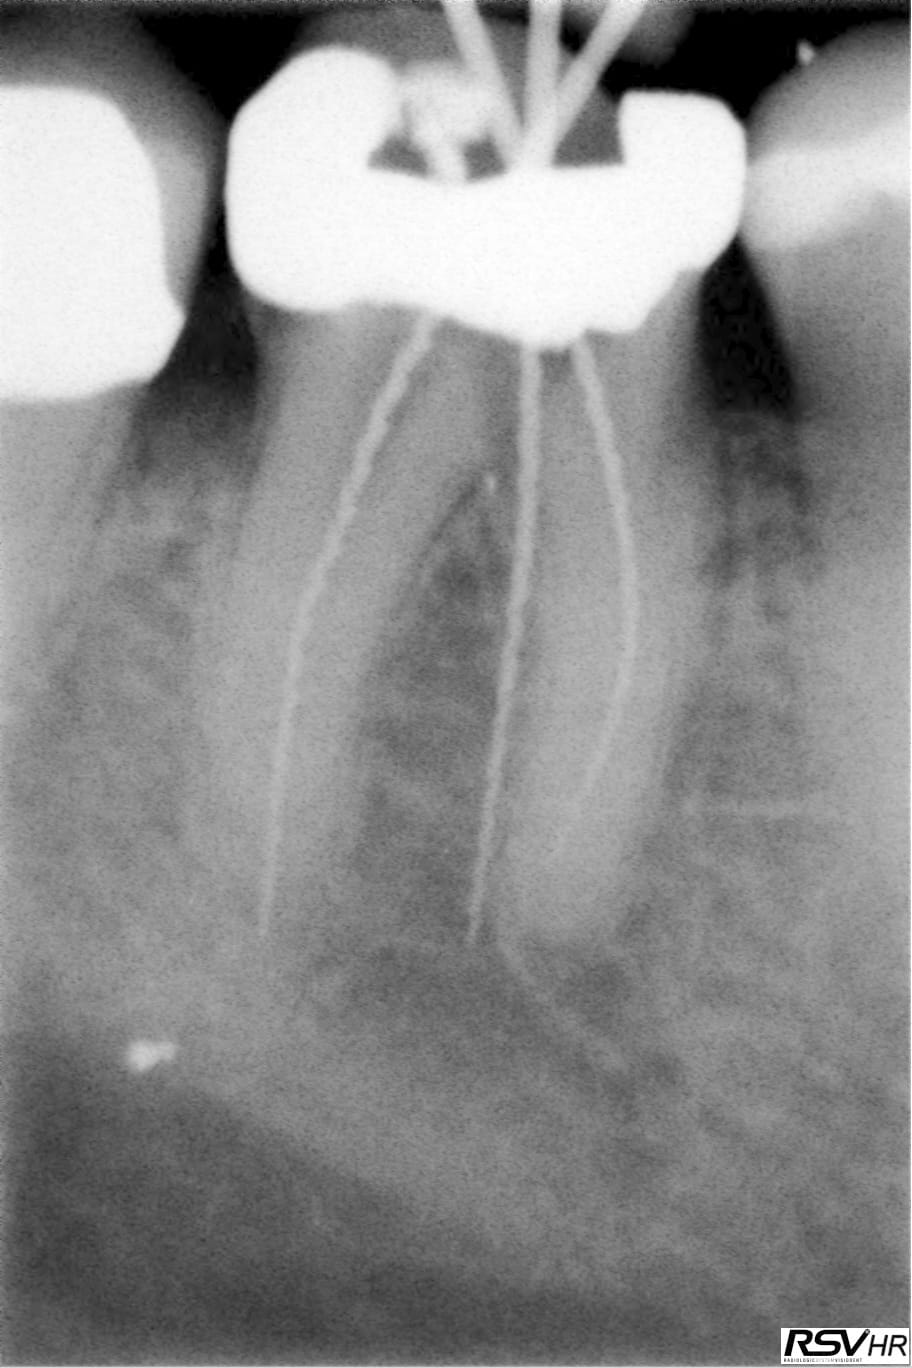

Exemple perfo magistrale en 2009, et radio 2013 et 2017 (on ne vois que la racine mésiale mais la furcation tient le coup.

46 2009 2 fujwq5 - Eugenol

46 2017 ra1wjf - Eugenol

46 2013 rwugpl - Eugenol

46 2009 cxmhe5 - Eugenol

Merci pour les photos.cela ressemble à ce qui s'est passé pour moi.j'ouvre tes la chambre avec une fraise endormi z donc je n'avais jamais eu de soucis de perfo sur une ouverture de chambre.